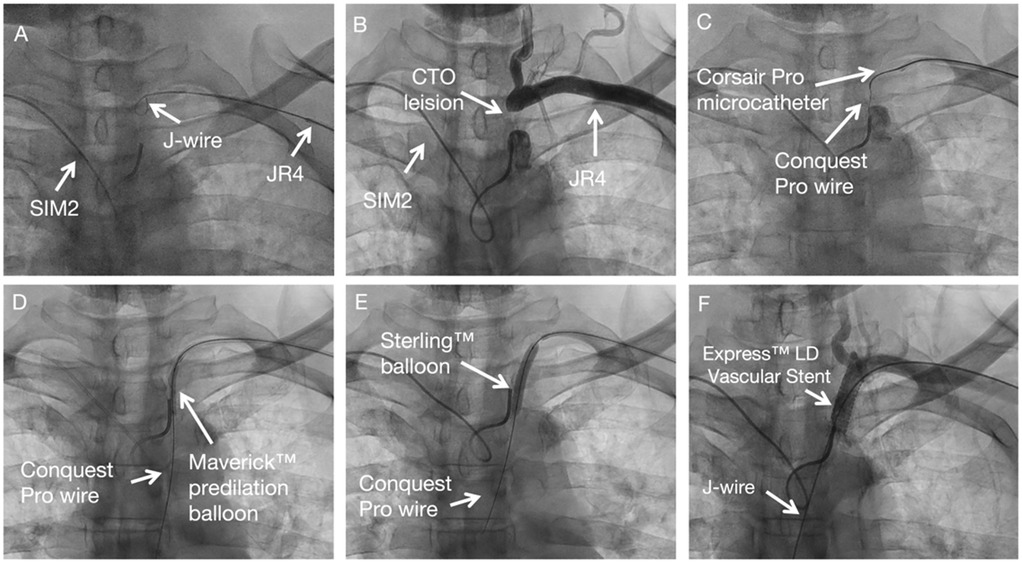

SIM 2 catheter from right-hand access engaged in the proximal cap of left subclavian artery stenosis and JR 4 advanced over J wire from the left hand access to the distal cap of left subclavian artery stenosis (Figure 2A). A diagnostic angiogram by SIM 2 catheter from right-hand access and JR 4 from left hand access showing proximal left subclavian artery stenosis total occlusion (Figure 2B). Corsair Pro microcatheter was used with a Conquest Pro wires to successfully cross the lesion retrogradely (Figure 2C). Contrast injection from SIM 2 to confirm the recanalization. Free movement of SIM 2 catheter over the Conquest Pro wire. Balloon angioplasty was performed with a Maverick™ 3.0 × 20 mm at 8 atm (Figure 2D). Balloon angioplasty was performed with a Sterling™ 5.0 × 30 mm balloon at 8 atm (Figure 2E). The Conquest Pro wire was then exchanged for a 260 cm J-wire from left hand access. An Express™ LD Vascular Stent 8.0 × 27 mm was delivered without a guide catheter and positioned across the lesion. The stent was carefully deployed at normal pressure (10 atm) without repositioning of the x-ray table to prevent displacement. The stent was fully expanded. Stent expansion, vessel wall apposition, and the absence of edge dissection were confirmed by angiography from SIM2 and showed no residual stenosis (Figure 2F). Technical details are available in the Supplementary Material 1.

Figure 2. Subclavian stenting procedure method of CTO subclavian stenosis. (A) Diagnostic angiogram defining the occlusion. (B–C) Retrograde crossing of the lesion with a microcatheter and wire. (D–E) Sequential balloon angioplasty. (F) Final result after stent placement, showing no residual stenosis.